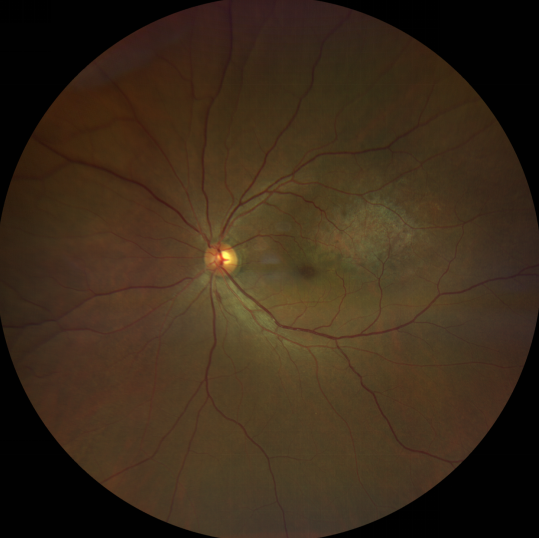

脈絡膜黑色素瘤是成年人常見的眼內(nèi)惡性腫瘤,其患病率在我國居眼內(nèi)惡性腫瘤的第二位,僅次于視網(wǎng)膜母細胞瘤。其惡性程度高,不僅可致患者喪失視力,而且嚴重威脅患者生命,即使在沒有明確轉(zhuǎn)移前摘除患眼眼球,其5年死亡率也有17%-53%。

脈絡膜黑色素瘤是葡萄膜惡性腫瘤中較多的一種。葡萄膜腫瘤主要發(fā)生于脈絡膜、睫狀體和虹膜。其中,脈絡膜腫瘤占80%,睫狀體腫瘤占12%,虹膜腫瘤占8%。惡性程度高的腫瘤主要發(fā)生于脈絡膜。發(fā)生于睫狀體的腫瘤惡性程度偏低,發(fā)生于虹膜的腫瘤多數(shù)為良性。脈絡膜黑色素瘤的特點是惡性程度高、易侵襲轉(zhuǎn)移、預后極差,嚴重威脅患者的視力和生命。其發(fā)病率有種族差異性,以高加索及白種人居多,黑人發(fā)病率低,亞洲人居于中間。

脈絡膜黑色素瘤患者在發(fā)病早期無眼痛等癥狀,當腫瘤較小時較難發(fā)現(xiàn),隨著病程進展,腫瘤增大,發(fā)生滲出性視網(wǎng)膜脫離或累及黃斑,視力下降才就診。

脈絡膜黑色素瘤惡性程度高,50%的患者會發(fā)生轉(zhuǎn)移,轉(zhuǎn)移到肝、肺等遠處臟器,常見的轉(zhuǎn)移方式是經(jīng)鞏膜導管擴散,經(jīng)視神經(jīng)蔓延者罕見。一旦發(fā)生轉(zhuǎn)移,1年生存率只有10%,即絕大多數(shù)病人在半年至1年間會失去生命。因此,早期診斷和選擇合適的治療方式對有效提高局部腫瘤的控制率、降低腫瘤的遠處轉(zhuǎn)移率、延長患者的生存率具有重要意義。